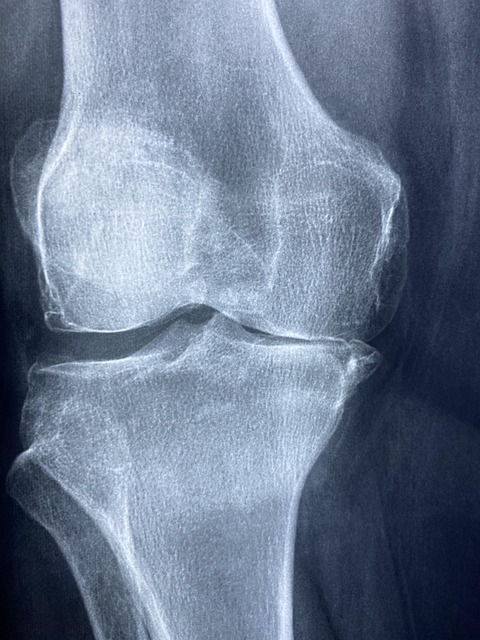

콘드로이친은 퇴행성 관절염(특히 무릎 관절염)의 증상 완화에 도움을 줄 수 있습니다. 연구에 따르면, 콘드로이친은 연골의 파괴를 늦추고, 연골 복원을 촉진하여 관절 통증을 줄여주는 효과가 있습니다. 주기적인 복용을 통해 움직임의 자유로움과 통증 완화를 경험할 수 있습니다.

연골은 시간이 지나면서 자연스럽게 마모되고 퇴화됩니다. 콘드로이친은 연골을 재생시키고 강화하는 데 도움을 줍니다. 따라서 관절의 유연성과 움직임을 높이는 데 중요한 역할을 합니다. 고령층, 무릎이나 엉덩이 관절에 부담이 많은 사람에게 매우 유익한 성분입니다.

콘드로이친은 연골의 구성 성분을 보충하고, 손상된 연골의 재생을 촉진하는 역할을 합니다. 특히, 연골에 충분한 수분을 공급하여 마르거나 갈라지는 것을 방지하고, 관절이 부드럽고 유연하게 움직일 수 있게 돕습니다.